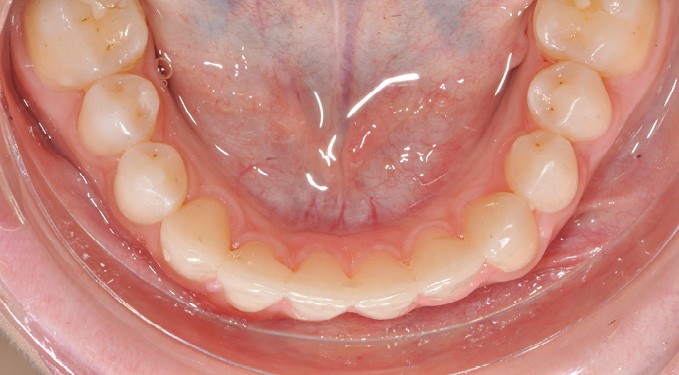

Par exemple, le retraitement d’un patient atteint d’un « Syndrome du fil » [2, 3], au vu de l’état des connaissances imparfaites de l’étiologie de cette situation, méritera une réflexion pour trouver un système de confiance. Une fibre collée est l’une des solutions sécurisantes (fig. 1). Mais, si la langue n’est pas stabilisée au repos comme en fonction, un dispositif amovible type Spring Retainer sera préférable.